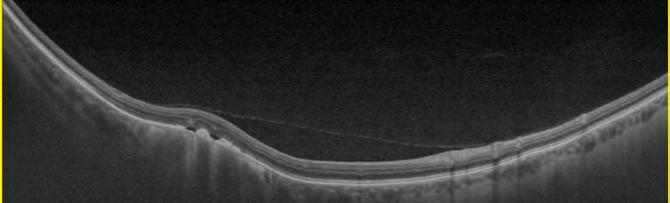

I started teaching at the end of 2020, as a visiting clinical tutor at City, University of London. Through City, I met Giovanni Montesano, a research fellow with the Crabb Lab. I started working as his research assistant, and we also co-led a separate project. The research looked at structural perimetry, using optical coherence tomography data to determine the starting points of the visual field test, aiming to make it quicker and more accurate. We presented at the Imaging and Perimetry Society, and won an award. That was a monumental moment, because I’d never presented my own work before. With optometry, once you go in one door it opens others. It’s nice to say yes to any opportunity. You never know where it will lead.